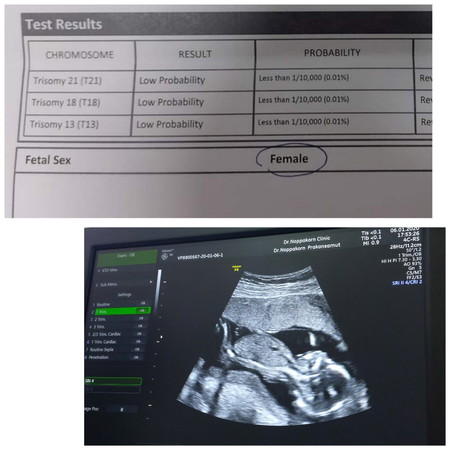

เมื่อวานไปฟังผลตรวจ สรุปคือความเสี่ยงเรื่องความผิดปกติของโครโมโซมต่ำ ทารกปลอดภัย99%ค่ะ ได้ยินแค่นี้ก็สบายใจแล้ว ครั้งนี้คุณหมอฟังเสียงหัวใจอย่างเดียว หัวใจเต้นปกติดี และก็ได้รู้เพศลูกด้วย สรุปว่า ผู้หญิง ค่าาา ♀️♀️♀️